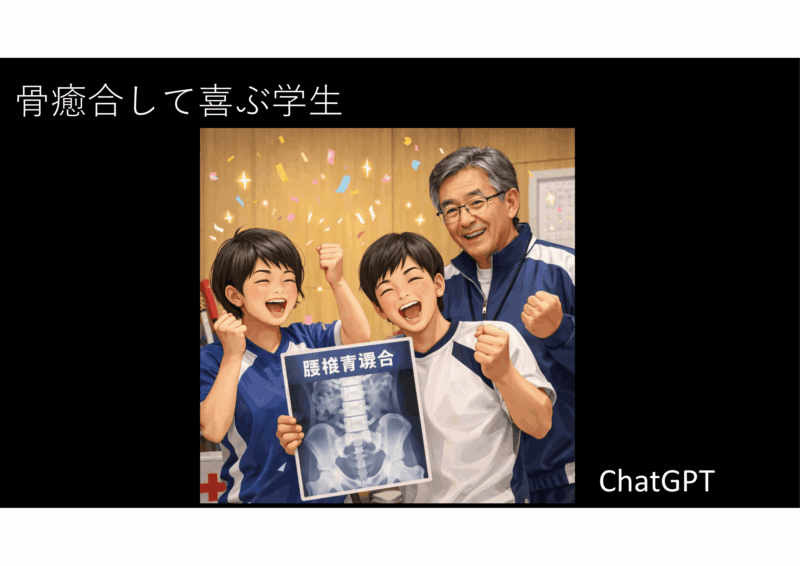

診断は初期腰椎分離 西良教授の結果では3か月安静、硬性コルセットで>90%骨癒合

しかし、実際はもっと癒合しない子が多いです。ほかの脊椎外科医としゃべると、「90%はなー、ちと高い」、となります。リハとのカンファでは、結構、安静ができていない可能性が示唆されました。今、データをとっているところですが、確信があります。

「分離初期です。治るチャンスのある状態という事です。硬性コルセットを作成し、装着することで、壁のポスターのように3か月安静で90%は癒合するとされていますが、経験ではもっと癒合率は低いです。リハビリで体幹筋力、腰椎周辺の筋・関節の柔軟性を診ます。そして腰椎に負担のない、一生運動できる身体づくりを目指します。